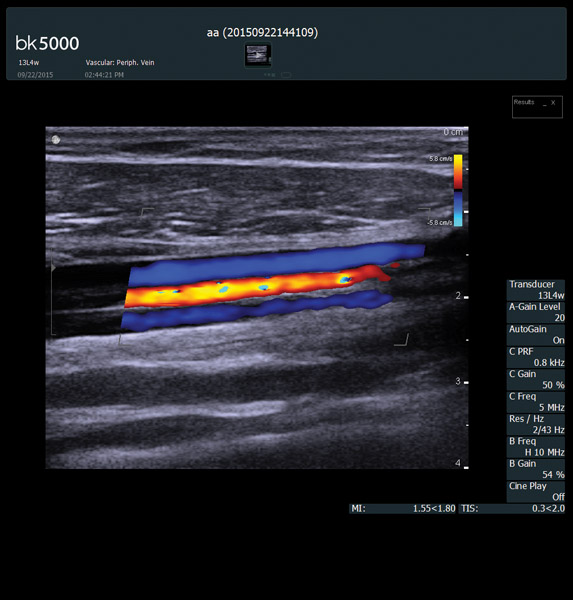

You know what you need, and you need it fast. That’s why the bk5000 is designed to deliver the high resolution images you count on quickly and efficiently. Whether you’re identifying margins of a lesion or making a general assessment of an area of interest, the bk5000 has the power and performance to meet your needs on your terms.